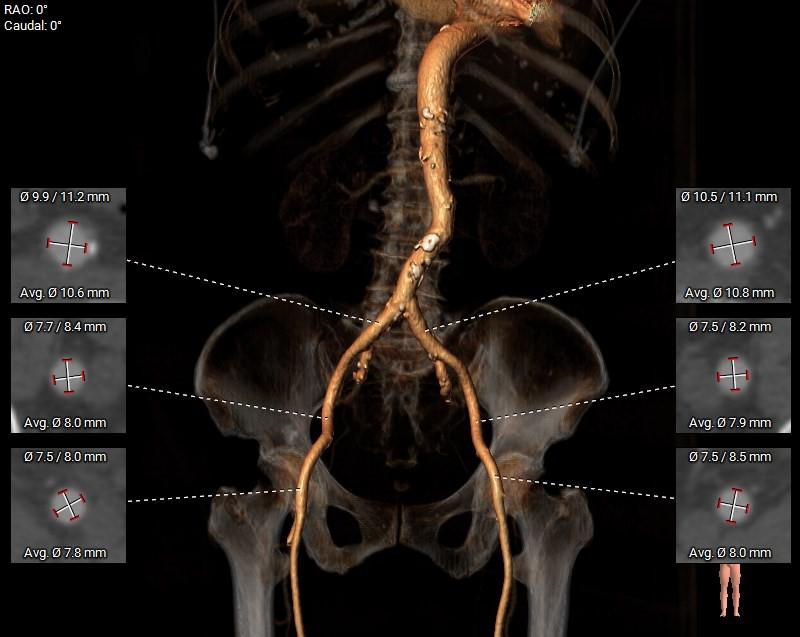

外周入路

◇ 外周入路血管走形迂曲,降主动脉有较锐夹角,主动脉弓,降主动脉,胸主动脉,腹主动脉有附壁钙化分布,血管内径可。